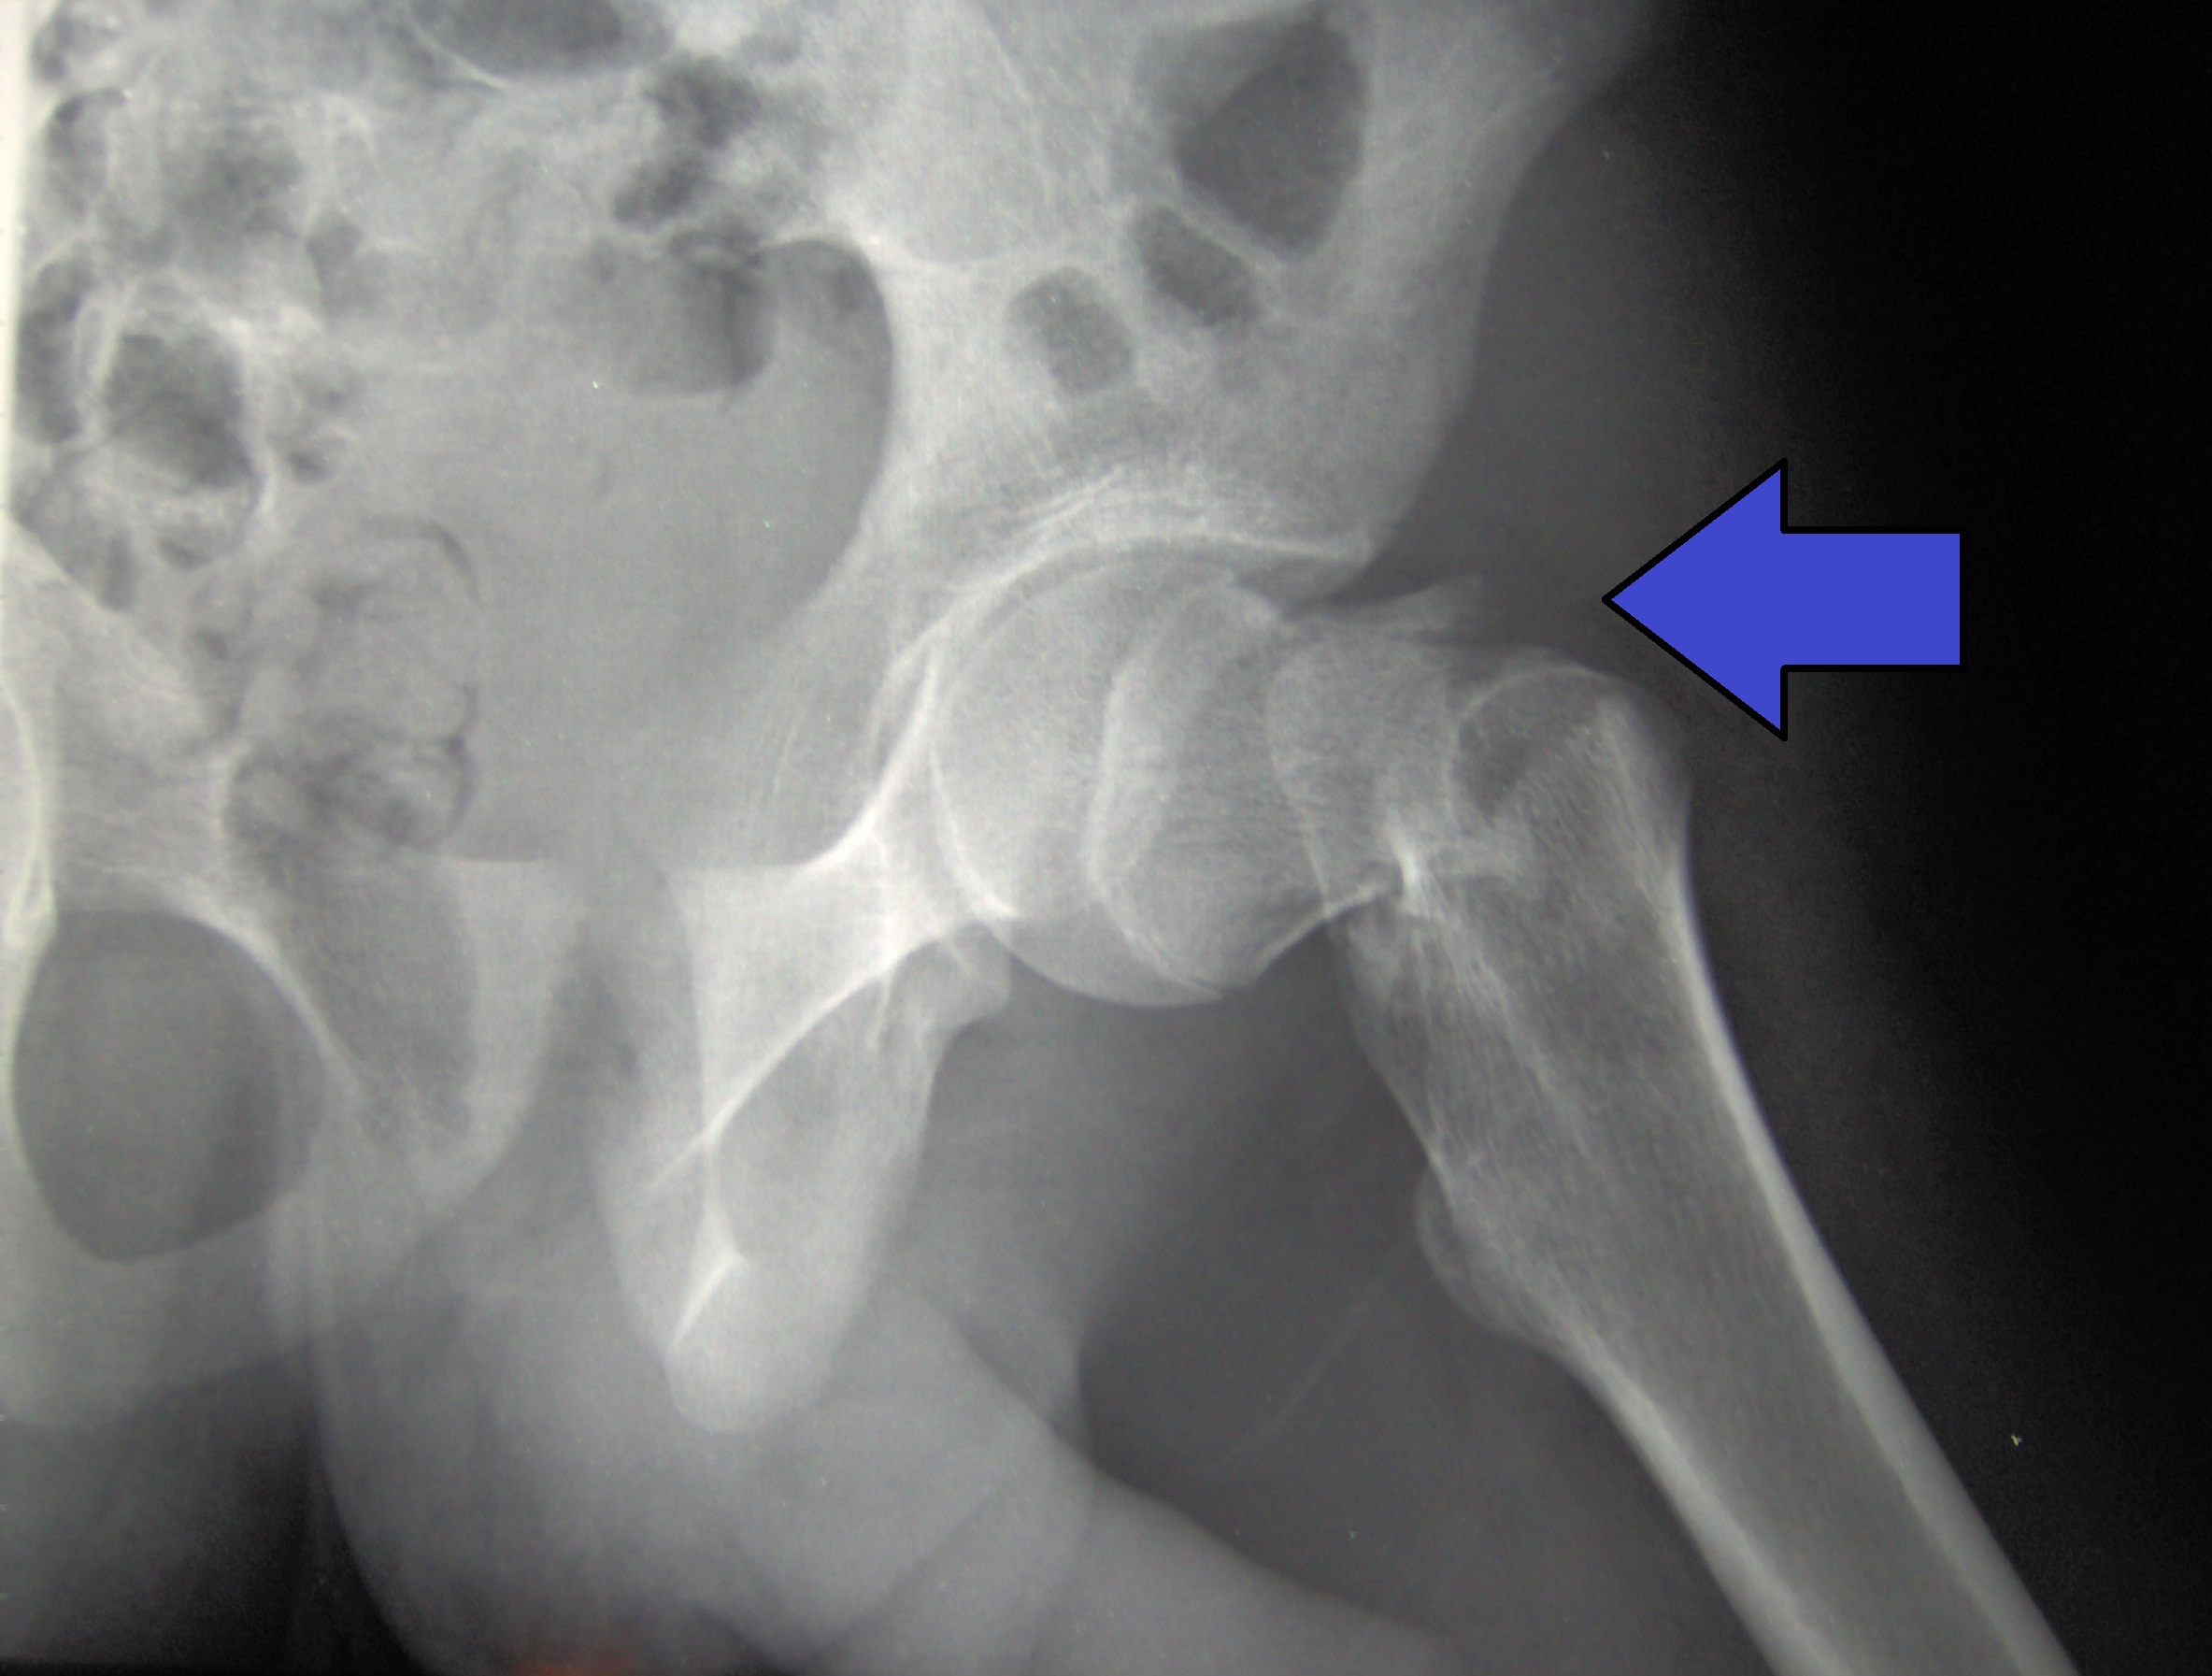

Alendronato para la prevención primaria y secundaria de las fracturas osteoporóticas en mujeres posmenopáusicas

Para la prevención primaria, en comparación con placebo, el alendronato 10 mg/día podría reducir las fracturas vertebrales y no vertebrales clínicas, pero podría lograr poca o ninguna diferencia en las fracturas de cadera y muñeca, los retiros debido a eventos adversos y los eventos adversos graves. Para la prevención secundaria, el alendronato probablemente reduce las fracturas vertebrales clínicas y podría reducir las fracturas no vertebrales, de cadera y muñeca, así como los eventos adversos graves, en comparación con placebo. La evidencia del efecto del alendronato sobre las retiradas por eventos adversos es muy incierta. Cochrane Database Syst Rev. 27 de enero de 2025